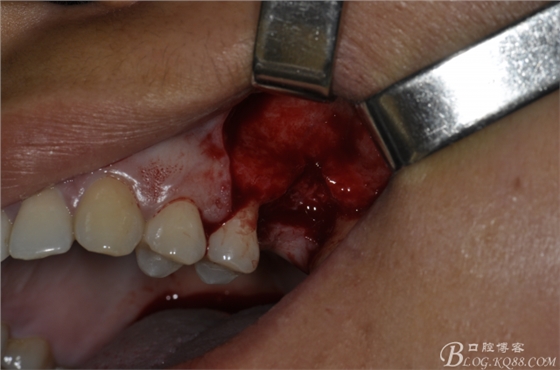

術(shù)前口內(nèi)照片。